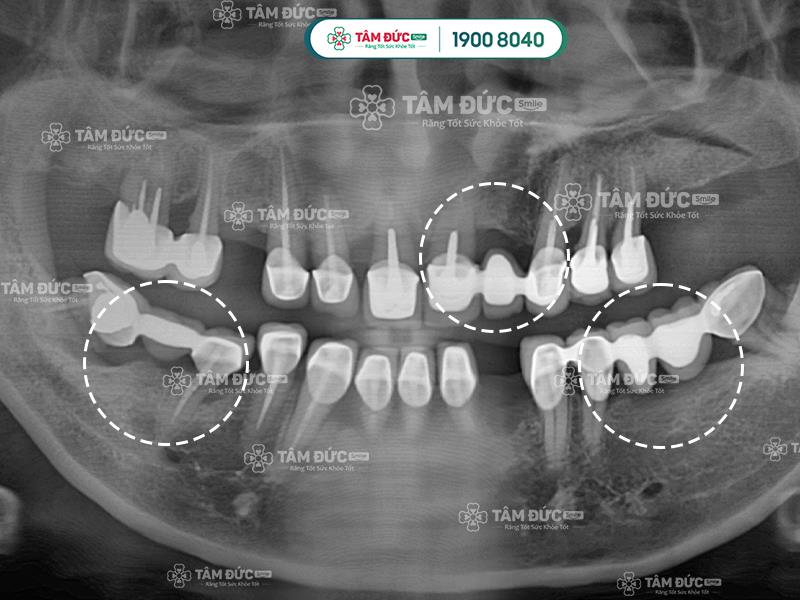

Phương pháp trồng răng Implant ngăn chặn tiêu xương hàm hiệu quả hơn làm cầu răng sứ